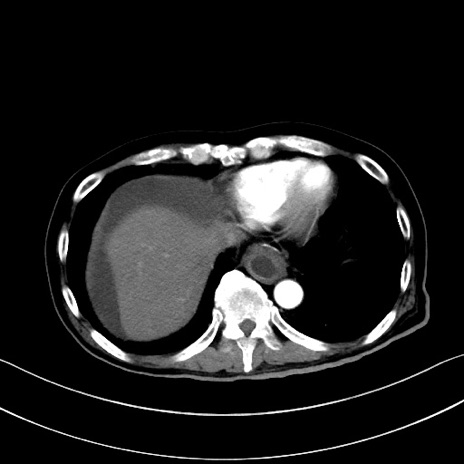

症例28(横断像)

【症例】60歳代男性

【主訴】嘔吐

【現病歴】胃癌にて胃全摘後。食思不振が悪化し、夜中に嘔吐することがある。

【既往歴】胃癌、胃全摘、脾摘、胆摘後

【データ】WBC 5900、CRP 10.56